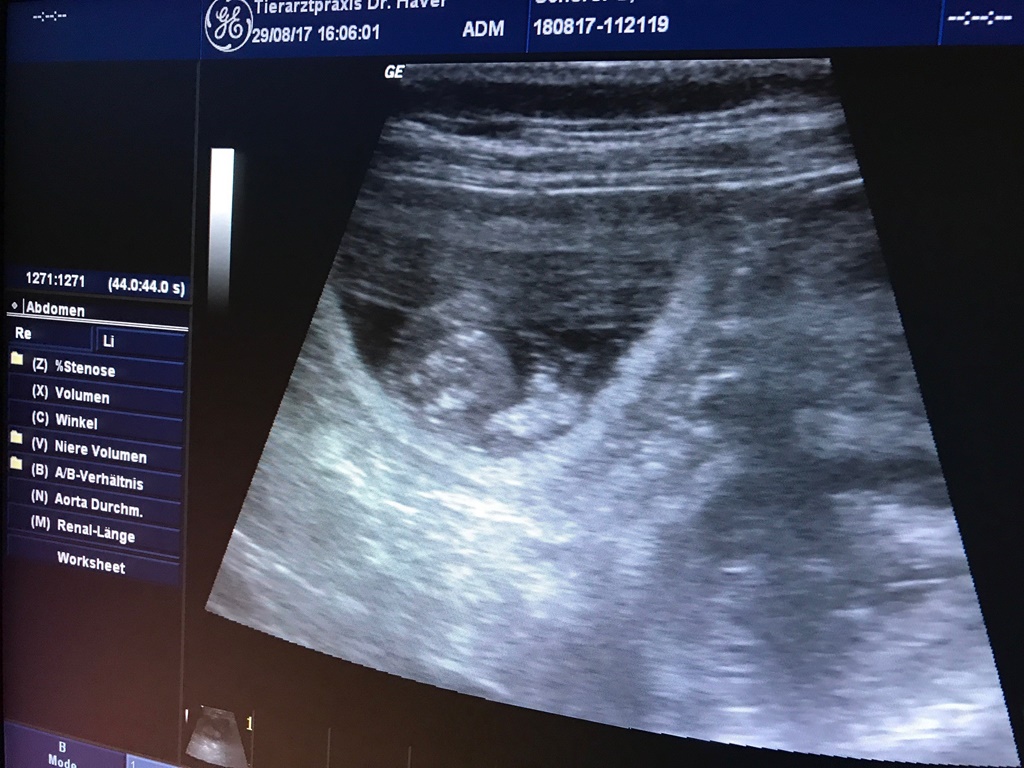

Bruna's Ultraschall

GROSSARTIGE NEUIGKEITEN!

Die Ultraschalluntersuchung hat hervorragende Neuigkeiten gebracht!

Wir freuen uns und halten Euch auf dieser Seite auf dem Laufenden!